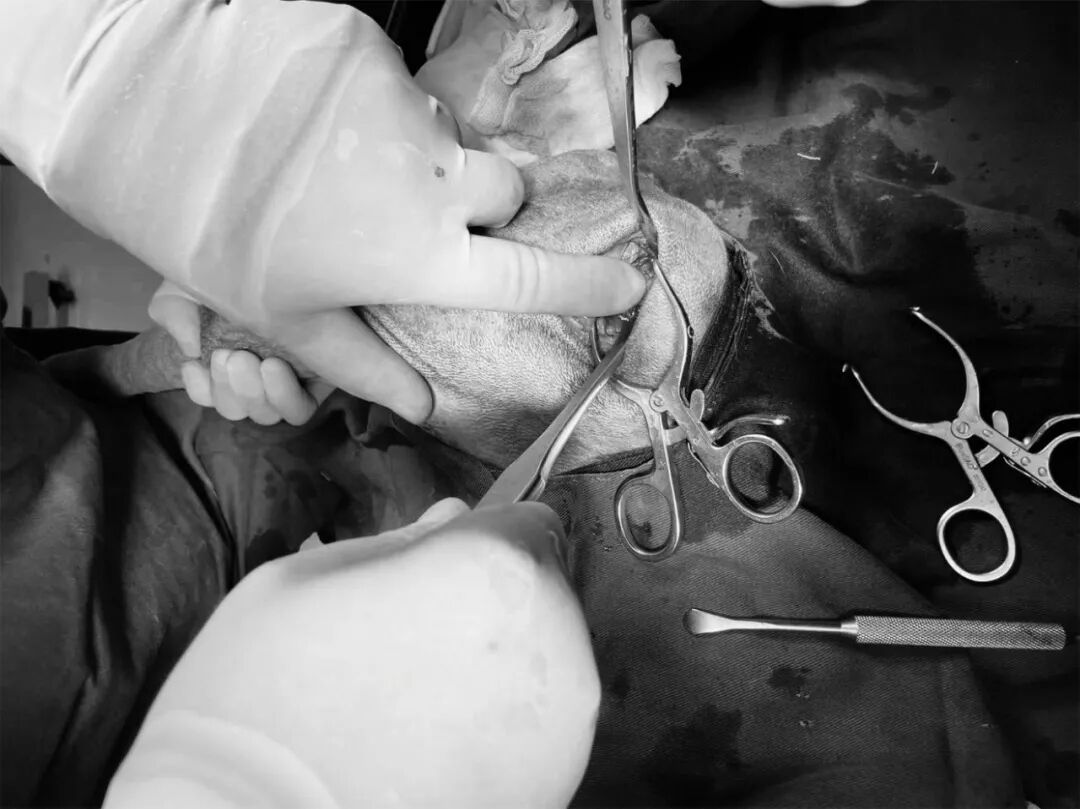

10、剪开阔筋膜张肌

动物拍片腹部怎么摆【病例分享】犬-外科-股骨头切除术_https://www.jmylbn.com_新闻资讯_第19张